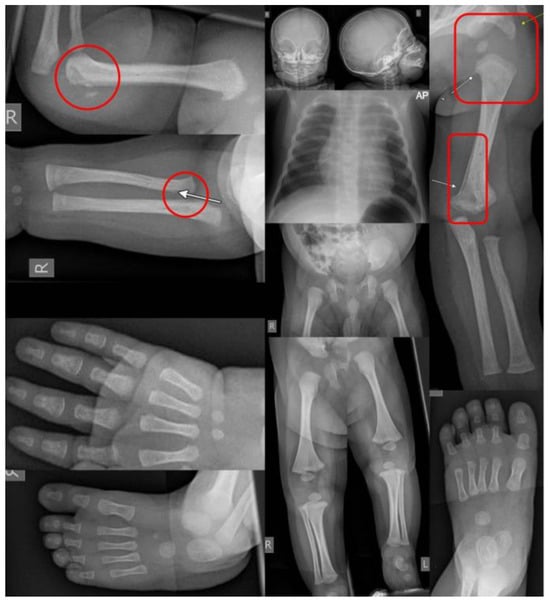

A skeletal survey (SS) is a core component in the workup of patients suspected of NAT that involves the evaluation of the entire skeletal system for fractures (Figure 2). For children under two years old or those unable to communicate due to disability, the SS is universally recommended [11,14,26,27]. There is no standardized number of views required for a SS, and guidelines vary from 17 to 32 views, with an average of 20 views [26,28]. In general, orthogonal views of the entire axial and appendicular skeleton are recommended. Additionally, oblique views of the ribs are almost universally recommended [10,26,27,28,29,30]. Overall, this workup is considered low radiation with a dose of 0.2 mSV (millisievert) [28]. The use of SS has been quoted to identify occult fractures in up to a fourth of patients [31]. Additionally, many experts and organizations advocate for a repeat skeletal survey at an interval of 1–4 weeks in order to better identify occult fractures that become more apparent after callus formation begins [14,26,28]. This repeat SS typically contains fewer views than the primary SS with half of the radiation [28]. Unfortunately, despite the benefits of the repeat SS and expert recommendations for its use, compliance with this recommendation is reported to be low [28,31].

Figure 2. A skeletal survey of a four-month-old brought in with an inability to move the right arm, allegedly after the older sibling fell on top of him. The skeletal survey showed fresh corner fractures of the humerus and radius on the right (circle highlights) and signs of older fractures on the left (rectangular highlights), a combination that is pathognomonic for NAT.